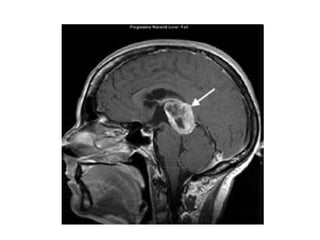

Imagem

• TC – identificação da hidrocefalia

• RM – melhor definição da lesão e limites